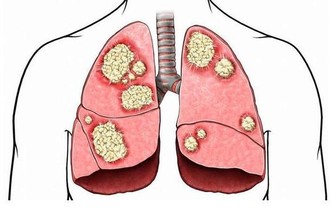

當體積過小時,腸道的蠕動減慢,糞便通過腸道的時間拉長,於是腸壁會吸收更多糞便中的水份,使得糞便越來越乾硬,更容易囤積腸子裡。

身體充足的含水量 有助排便糞便內容物的組成,大部分是不可溶性纖維(人體消化酵素無法分解),還有一小部分的死細胞與無法再處理的殘渣。不溶性纖維包括了木質素、纖維素與半纖維素等,富含於蔬菜與榖物之中。不溶性纖維會在大腸內吸收水份,使得糞便體積增加,促進排便,縮短糞便通過腸道的時間。因此,身體的含水量也非常重要,每天有充分的飲水量,才能讓糞便的體積增加,並且防止腸壁細胞回收已經非常少的水份。